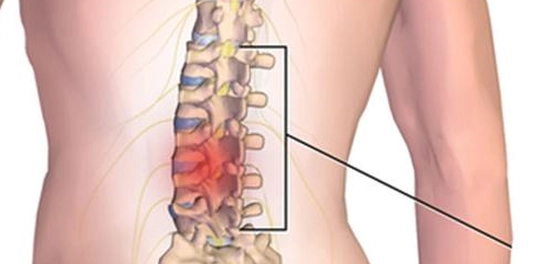

علامات عرق النسا

يُعدّ عرق النسا (Sciatica) من أكثر الأعراض شيوعاً المصاحبة للانزلاق الغضروفي القطني (Lumbar herniated disc)، المعروف أيضاً بالانزلاق الغضروفي في أسفل الظهر. ينجم هذا الألم عن ضغط على أحد الأعصاب أو أكثر من الأعصاب التي تغذي العصب الوركي (Sciatic nerve)، مما يُسبب ألماً، أو حرقة، أو وخزاً، أو تنملاً. تمتد هذه الأعراض عادةً من الأرداف إلى الساق، وقد تصل إلى القدم أحياناً. ومن الجدير بالذكر أن هذه الأعراض غالباً ما تُصيب جانب واحد من الجسم فقط. [1]